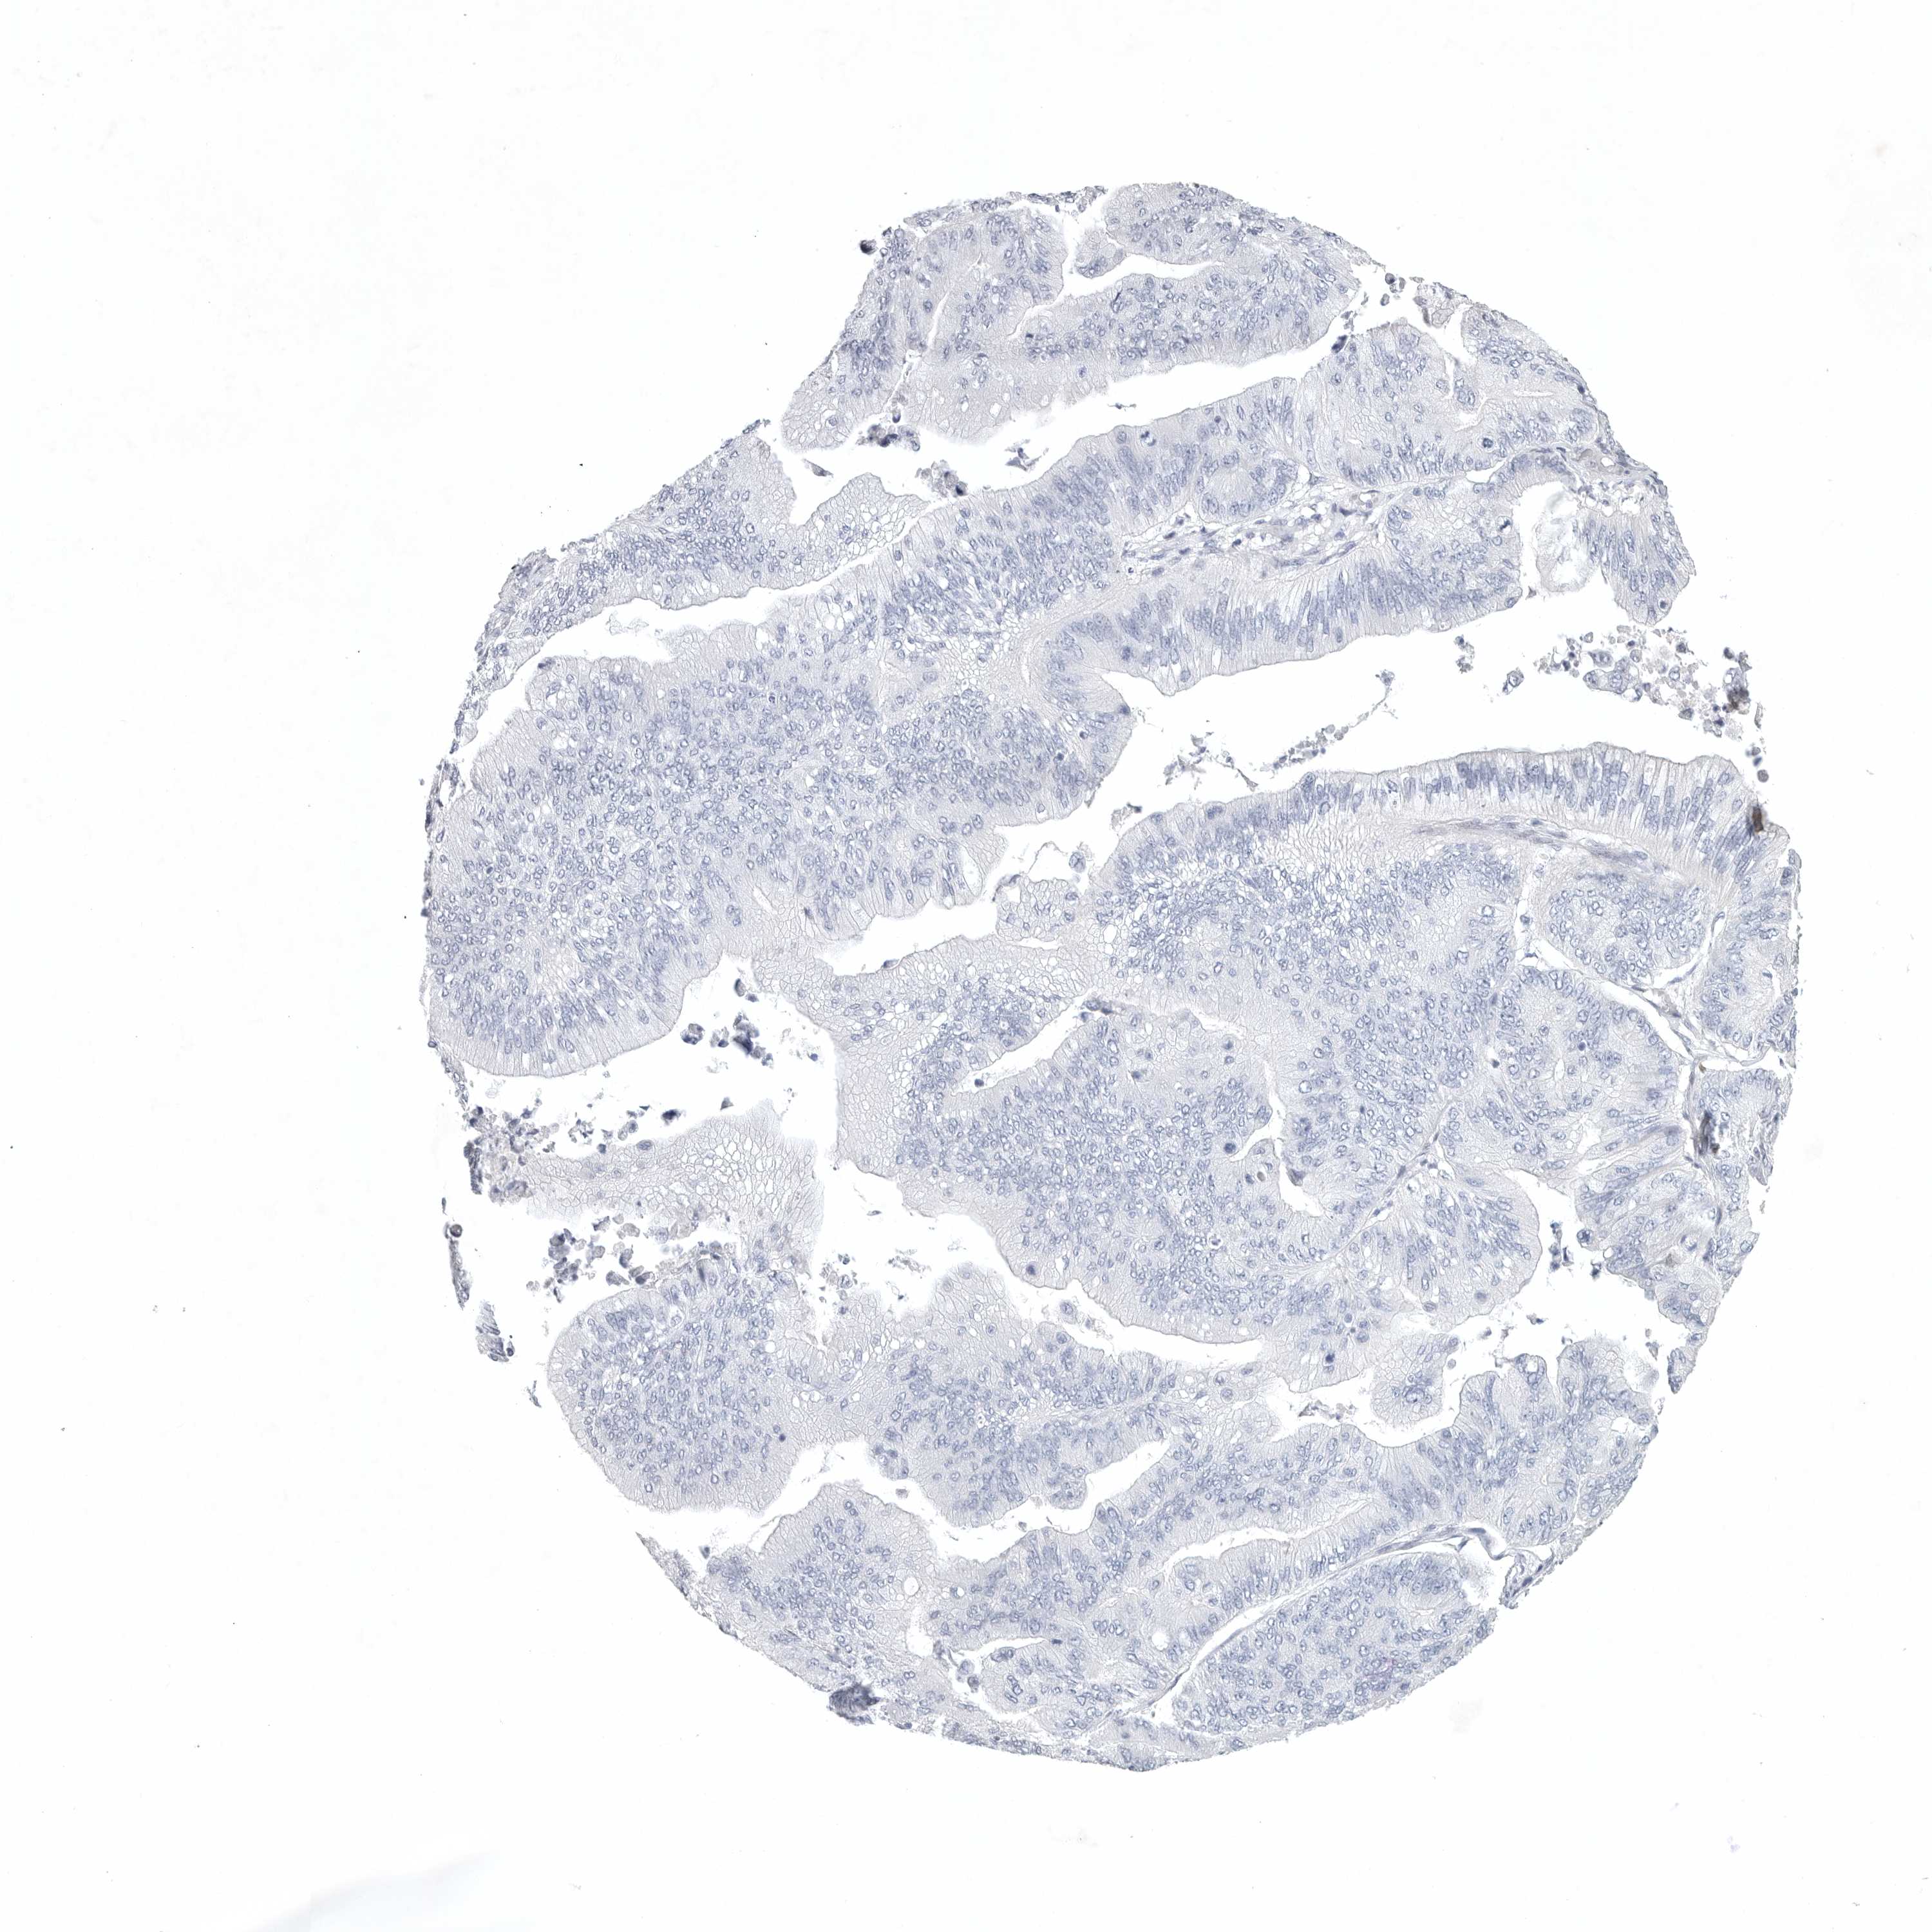

OVARIAN CANCER - Protein expressioni

A mouse-over function shows sample information and annotation data. Click on an image to view it in a full screen mode. Samples can be filtered based on level of antibody staining by selecting one or several of the following categories: high, medium, low and not detected. The assay and annotation is described here.

Note that samples used for immunohistochemistry by the Human Protein Atlas do not correspond to samples in the TCGA dataset.

Antibody stainingi

Antibody staining in the annotated cell types in the current human tissue is reported as not detected, low, medium, or high, based on conventional immunohistochemistry profiling in selected tissues. This score is based on the combination of the staining intensity and fraction of stained cells.

Each image is clickable and will lead to virtual microscopy that enables deeper exploration of all samples and also displays staining intensity scores, fraction scores and subcellular localization as well as patient and tissue information for each sample.

Antibody HPA027134

Antibody HPA027150

Antibody HPA029859

Antibody CAB022343

Cystadenocarcinoma, serous, NOS

Carcinoma, endometroid

Cystadenocarcinoma, mucinous, NOS

Carcinoma, NOS